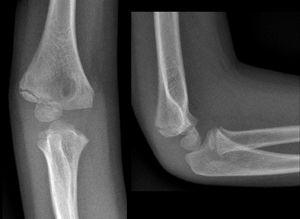

肱骨内上髁骨折能治好吗?

肱骨内上髁骨折是肘部损伤中最常见的一种,约占肘关节骨折的10%,仅次于肱骨髁上骨折与肱骨外髁骨折,占肘部损伤的第三位。骨折多发生在少年和儿童。肱骨内上髁骨折能治好吗?接下来跟大家分享下我的看法。

除Ⅰ度骨折一般不会移位外,其他类型骨折复位后不稳定,可发生再移位,在这种情况下,可采用闭合穿针固定;如骨折片有旋转,手法难以复位者,可采用经皮钢针撬拨复位,并用1~2枚克氏针作内固定,术后用石膏托或超关节小夹板外固定3~4周。

适用于骨折分离较明显,或骨折片嵌入关节腔手法难以解脱,旋转移位手法未能纠正及合并尺神经损伤者。合并尺神经挫伤应予以检查,如较严重可同时做尺神经前置手术。术后用石膏托固定4~5周,拆除石膏托拔除钢针后进行功能锻炼。

无移位的肱骨内上髁骨折,无需复位,仅用长臂石膏托或超关节小夹板固定3~4周,拆除石膏或夹板后进行功能锻炼。Ⅱ度以上骨折应先利用手法复位,失败者再手术。